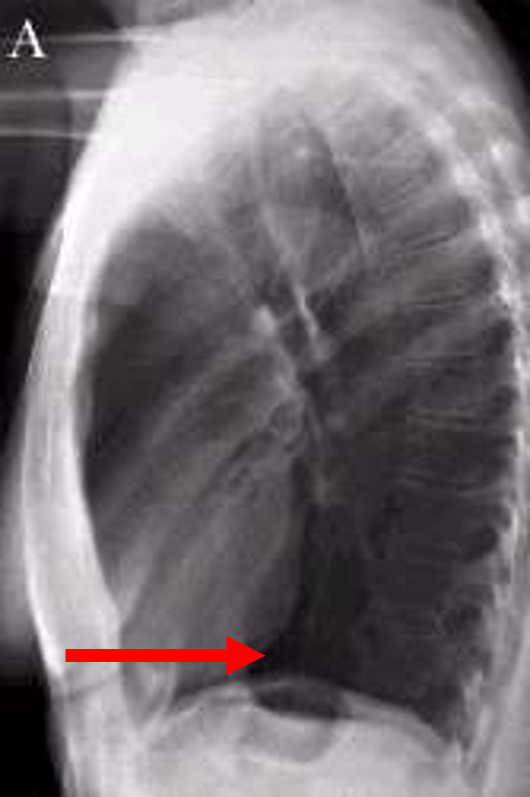

lateral chest

three rules of a lateral chest x ray

diaphragm shadow

retrosternal space

retrocardiac space